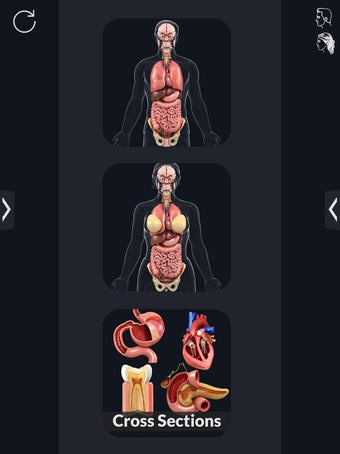

La interfaz fácil de usar de My Organs Anatomy permite una navegación sencilla, lo que facilita la selección, rayos X, ocultación y visualización de órganos individuales. La aplicación también incluye un modo de animación, opciones de búsqueda y un panel de información que proporciona información relacionada. Además, la aplicación ofrece pronunciación de audio para todos los términos anatómicos, e incluso los usuarios pueden dibujar o escribir en la pantalla y compartir capturas de pantalla.

En general, My Organs Anatomy es una gran aplicación para estudiantes de medicina y cualquier persona que quiera explorar la anatomía de los órganos humanos en detalle. Con sus gráficos de alta calidad y numerosas características, esta aplicación proporciona una excelente experiencia de aprendizaje para los usuarios.